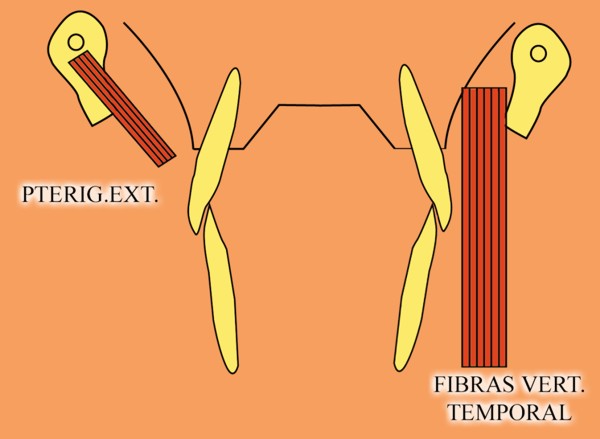

Sabemos que la fuerza desarrollada por el Pterigoideo Int. y el Masetero, músculos elevadores por excelencia, manifiestan durante el acto masticatorio su máxima expresión(LT), por lo tanto es evidente que dichas fuerzas soportadas fuera del eje axial de la pieza ,determinan grandes daños para las estructuras de soporte.